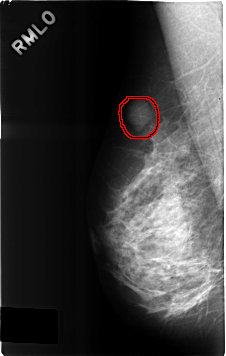

C_0308_1.RIGHT_MLO

RIGHT_MLO LINES 4616 PIXELS_PER_LINE 2936 BITS_PER_PIXEL 12 RESOLUTION 50 OVERLAY

FILE: C_0308_1.RIGHT_MLO.OVERLAY

TOTAL_ABNORMALITIES 1

ABNORMALITY 1

LESION_TYPE MASS SHAPE LOBULATED MARGINS CIRCUMSCRIBED

ASSESSMENT 3

SUBTLETY 4

PATHOLOGY BENIGN

TOTAL_OUTLINES 1

BOUNDARY